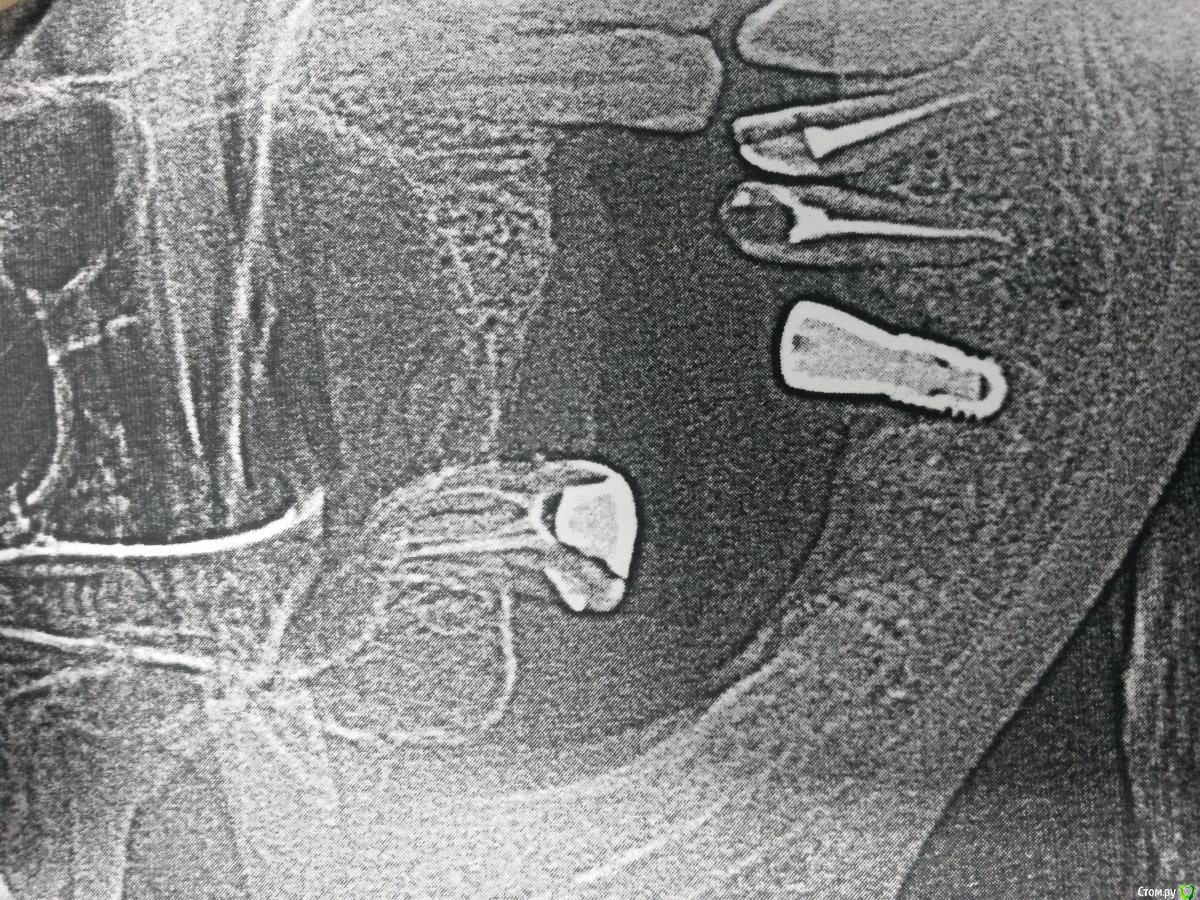

Nazim_NV86 Опубликовано 2 декабря, 2015 Поделиться Опубликовано 2 декабря, 2015 Почему он возник?Резал по гребню как обычно. Кость 1тип. 4.0х7мм. Торк 40. Шовный Викрил 5/0. Винты утоплены были в кость. Перегрев исключён. Ссылка на комментарий

Карен Аванесов Опубликовано 2 декабря, 2015 Поделиться Опубликовано 2 декабря, 2015 Ну что ж, погадаем. Инфекция раз. И верхний моляр как бэ на что то намекает. Ссылка на комментарий

gum Опубликовано 2 декабря, 2015 Поделиться Опубликовано 2 декабря, 2015 Почему вы берёте короткий имплантат и так его топите, можно и длиннее поставить вровень с костью. Периимплантит ? Грануляции нарушение стерилизации инструментов если уверены что не было перегрева и ишемии кости, мб у пациента есть соматическиепроблемы Ссылка на комментарий

alekszander Опубликовано 2 декабря, 2015 Поделиться Опубликовано 2 декабря, 2015 Почему вы берёте короткий имплантат и так его топите, можно и длиннее поставить вровень с костью. Периимплантит ? Грануляции нарушение стерилизации инструментов если уверены что не было перегрева и ишемии кости, мб у пациента есть соматическиепроблемы. Тут может на плоскостном снимке так кажется,иногда бывает при атрофии кости с одной из сторон,кажется что заглубил. У меня вопрос к топик кастеру - откуда уверенность, что не перегрел? Фрезы не тупые? Ну и гадать можно долго. Анамнез,анализы,протокол операции. Ссылка на комментарий

Nazim_NV86 Опубликовано 2 декабря, 2015 Автор Поделиться Опубликовано 2 декабря, 2015 Ну что ж, погадаем. Инфекция раз. И верхний моляр как бэ на что то намекает. моляр лечили недавно под штифтовкладку. З/о чищены. Имплант утоплен на 1мм вестибуло-орально. Стерилизацию инструментов не контролирую честно говоря. В сотрудниках уверен. Фрезы не новые точно. 3 набора в кабинете. Ссылка на комментарий

lonely_jack Опубликовано 3 декабря, 2015 Поделиться Опубликовано 3 декабря, 2015 (изменено) а какие внешние проявления? по таким снимкам диагноз бы не ставил, у нас такие на бумаге выдают самые дешевые городские поликлиники, на них и здоровые зубы с тааааакой периодонтальной щелью....обратите внимание, что вокруг формирователя вне кости - "периодонтальная щель". Может, артефакты? Изменено 3 декабря, 2015 пользователем lonely_jack 1 Ссылка на комментарий

Nazim_NV86 Опубликовано 4 декабря, 2015 Автор Поделиться Опубликовано 4 декабря, 2015 а какие внешние проявления? по таким снимкам диагноз бы не ставил, у нас такие на бумаге выдают самые дешевые городские поликлиники, на них и здоровые зубы с тааааакой периодонтальной щелью....обратите внимание, что вокруг формирователя вне кости - "периодонтальная щель". Может, артефакты? снимок и вправду с городской. Всё равно на днях открою рану для ревизии. Или не стоит? Ссылка на комментарий

Andre_ Опубликовано 4 декабря, 2015 Поделиться Опубликовано 4 декабря, 2015 снимок и вправду с городской. Всё равно на днях открою рану для ревизии. Или не стоит?может, продублировать снимок, а лучше здкт, прежде чем раскрывать... Ссылка на комментарий